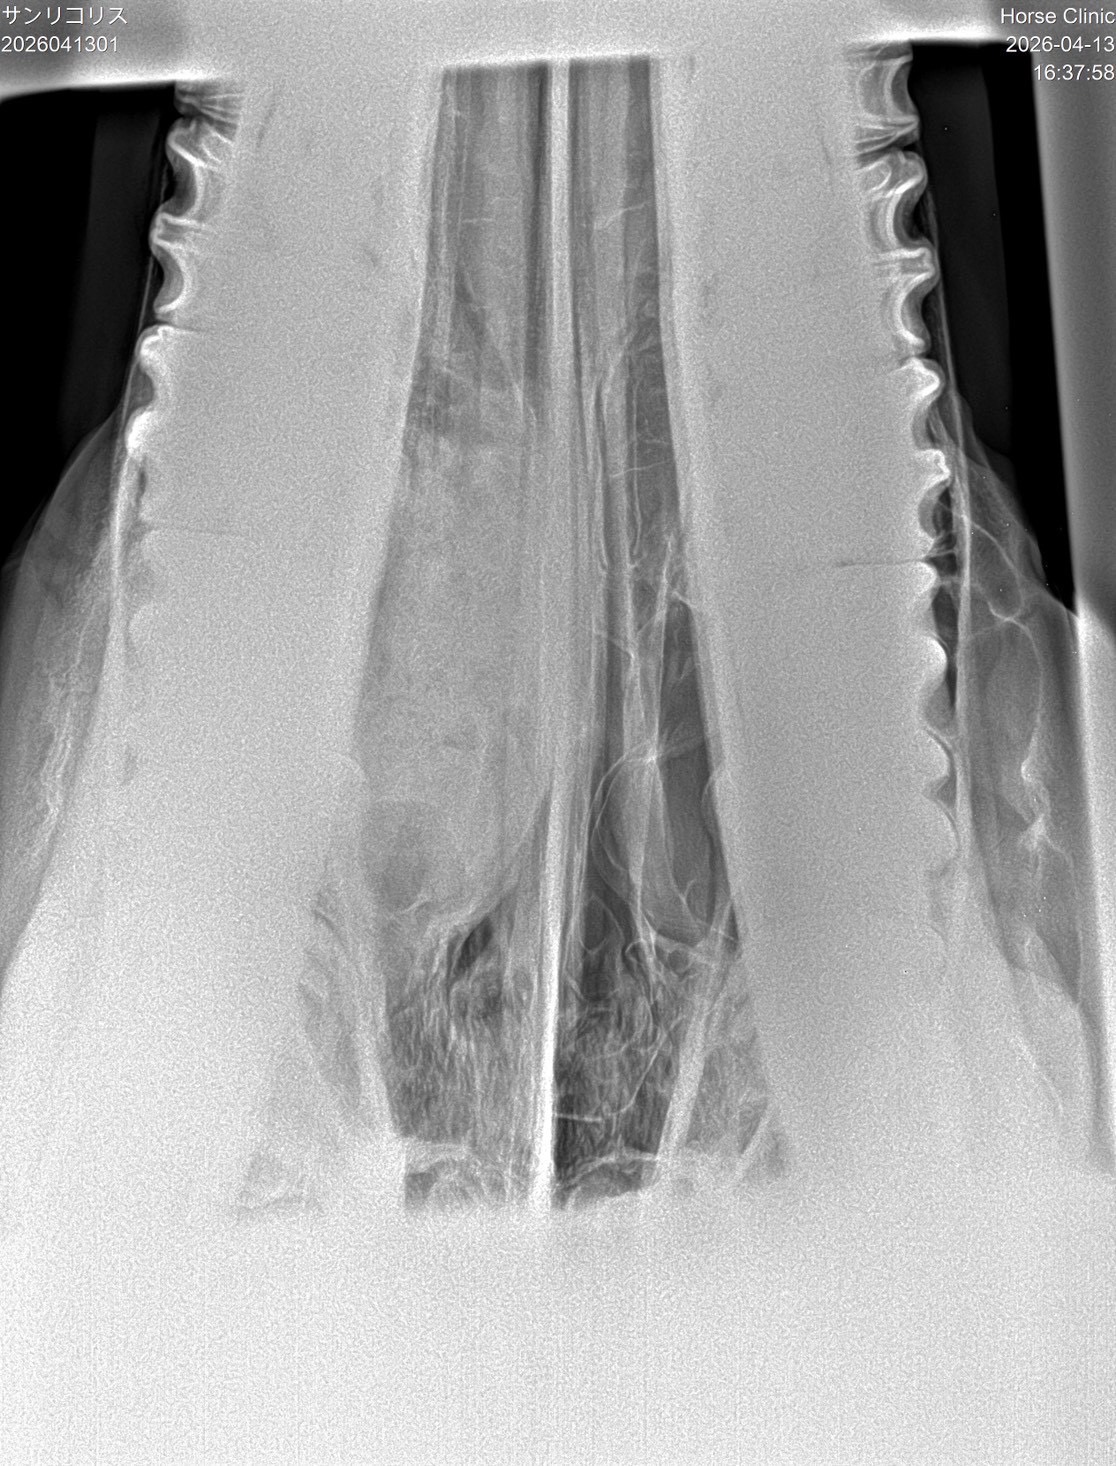

【本馬についての現状説明】

転厩当初から鼻水が止まらない状態で使っています。蓄膿症の症状で、治療は続けていますが、良くならないので、競馬でも影響が出ていると思います。頭数整理でオークション出品となりました。(川崎競馬・山崎裕也調教師)